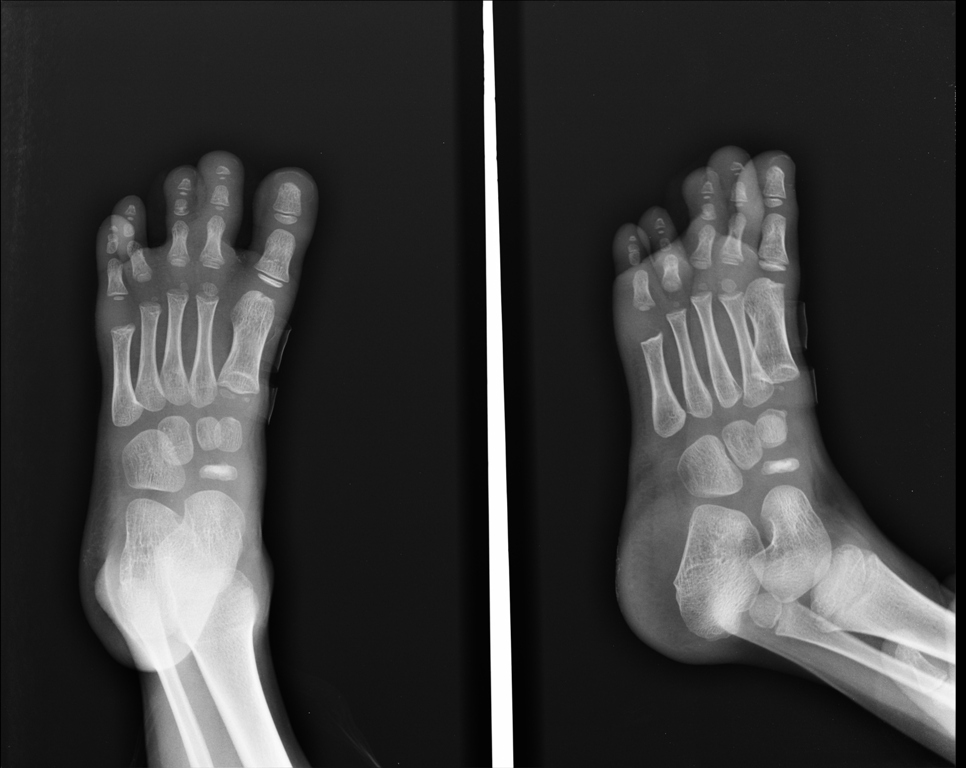

Η διάγνωση γίνεται με το ιστορικό, κλινική εικόνα και ακτινογραφία, η οποία μπορεί να δείξει κατακερματισμό του οστού. Αυτή όμως είναι συνηθισμένη εικόνα στη συγκεκριμένη ηλικία και μπορεί να αποτελεί απλά μία παραλλαγή του φυσιολογικού. Έτσι η ακτινογραφία αξιολογείται μόνο σε σχέση με τα συμπτώματα.